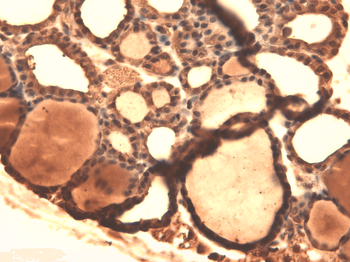

Immunohistochemical staining of paraffin embedded mouse ovary tissue using NIS antibody (2.5 ug/ml)

IHC-P image of mouse ovary tissue using NIS antibody (2.5 ug/ml)